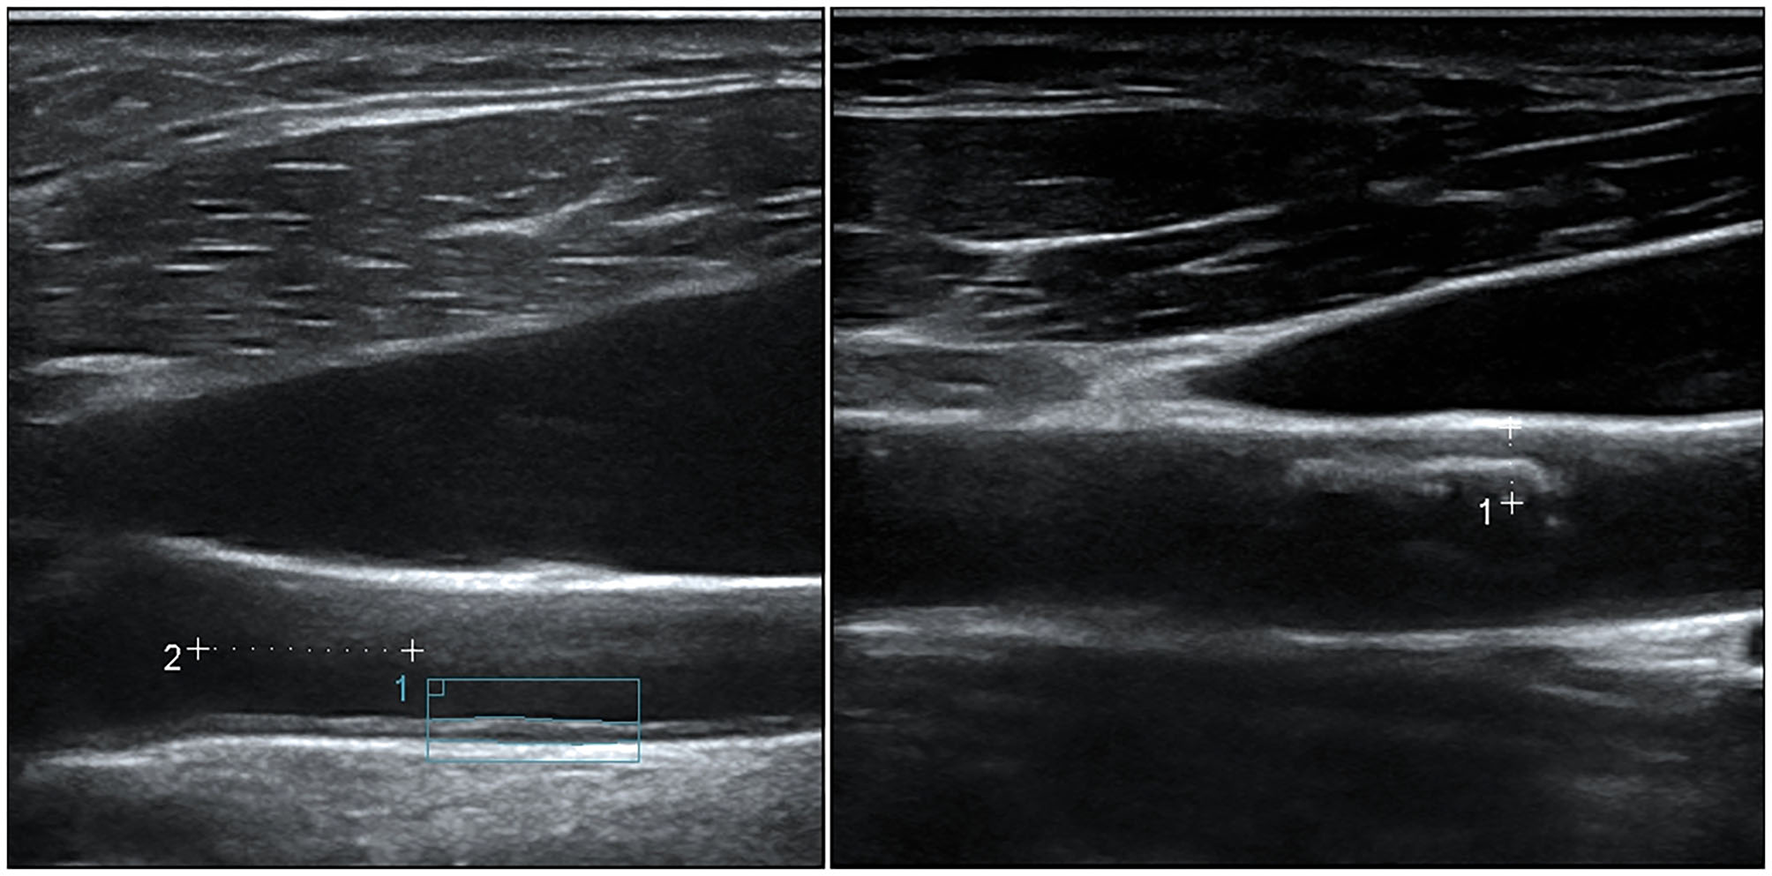

Carotid arteries were bilaterally scanned for increased IMT and presence of atheroma plaques, according to the Mannheim consensus (33) (Figure 2). Participants laid in a supine position with a mild hyperextension of the neck. Common carotids and their branches were scanned longitudinally and transversally for plaques, while IMT was measured longitudinally at common carotids.

Figure 2

Representative ultrasound features of carotid atherosclerosis. (Left) An increased intima-media thickness (1.048 mm), measured 1 cm proximal to the carotid bulb according to the Mannheim consensus. (Right) A partially calcified atheroma plaque (maximal thickness 3.1 mm) at the anterior wall of the common carotid artery.